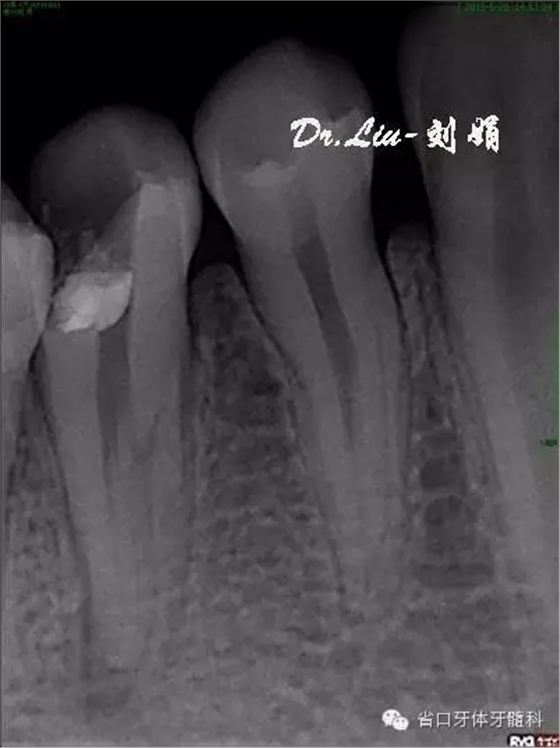

牙片顯示:45充填物至髓腔,根管內(nèi)無(wú)充填物影像,根管影像不清疑似多根管,根尖區(qū)見(jiàn)X線透射區(qū)。

圖1:術(shù)前X線片,根管影像不清,根尖區(qū)見(jiàn)X線透射區(qū)